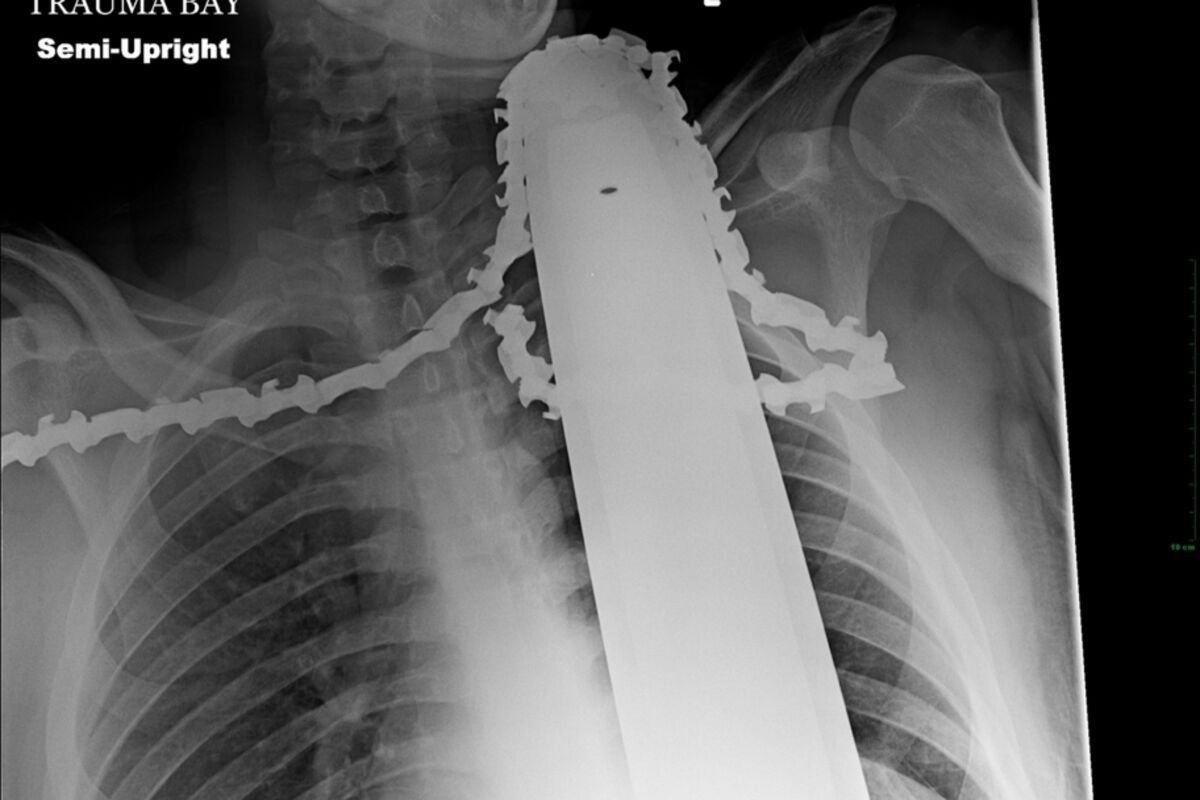

Po dolasku u bolnicu, Valentajn je hitno operisan. Doktori su saopštili da je lanac promašio velike krvne sudove, i povrijedio mu mišić. Bolnica je u utorak objavila rentgenski snimak na kojem se vidi lanac u vratu 21-godišnjeg drvosječe.